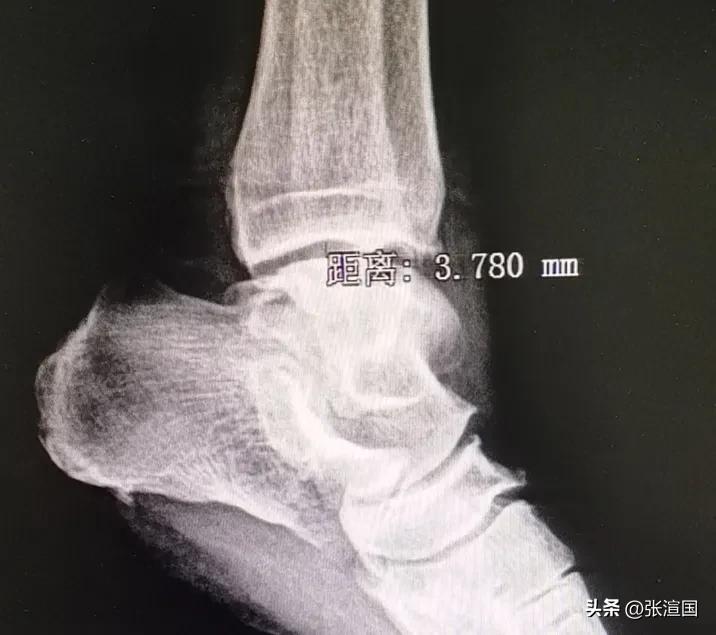

我接过单子,左踝关节正侧位,让老太太躺到诊断床上,拍了两张片子,观察后没有骨折,关节间隙也没有增宽,表明老太太只是轻微韧带拉伤。

踝关节:3.0~4.0mm